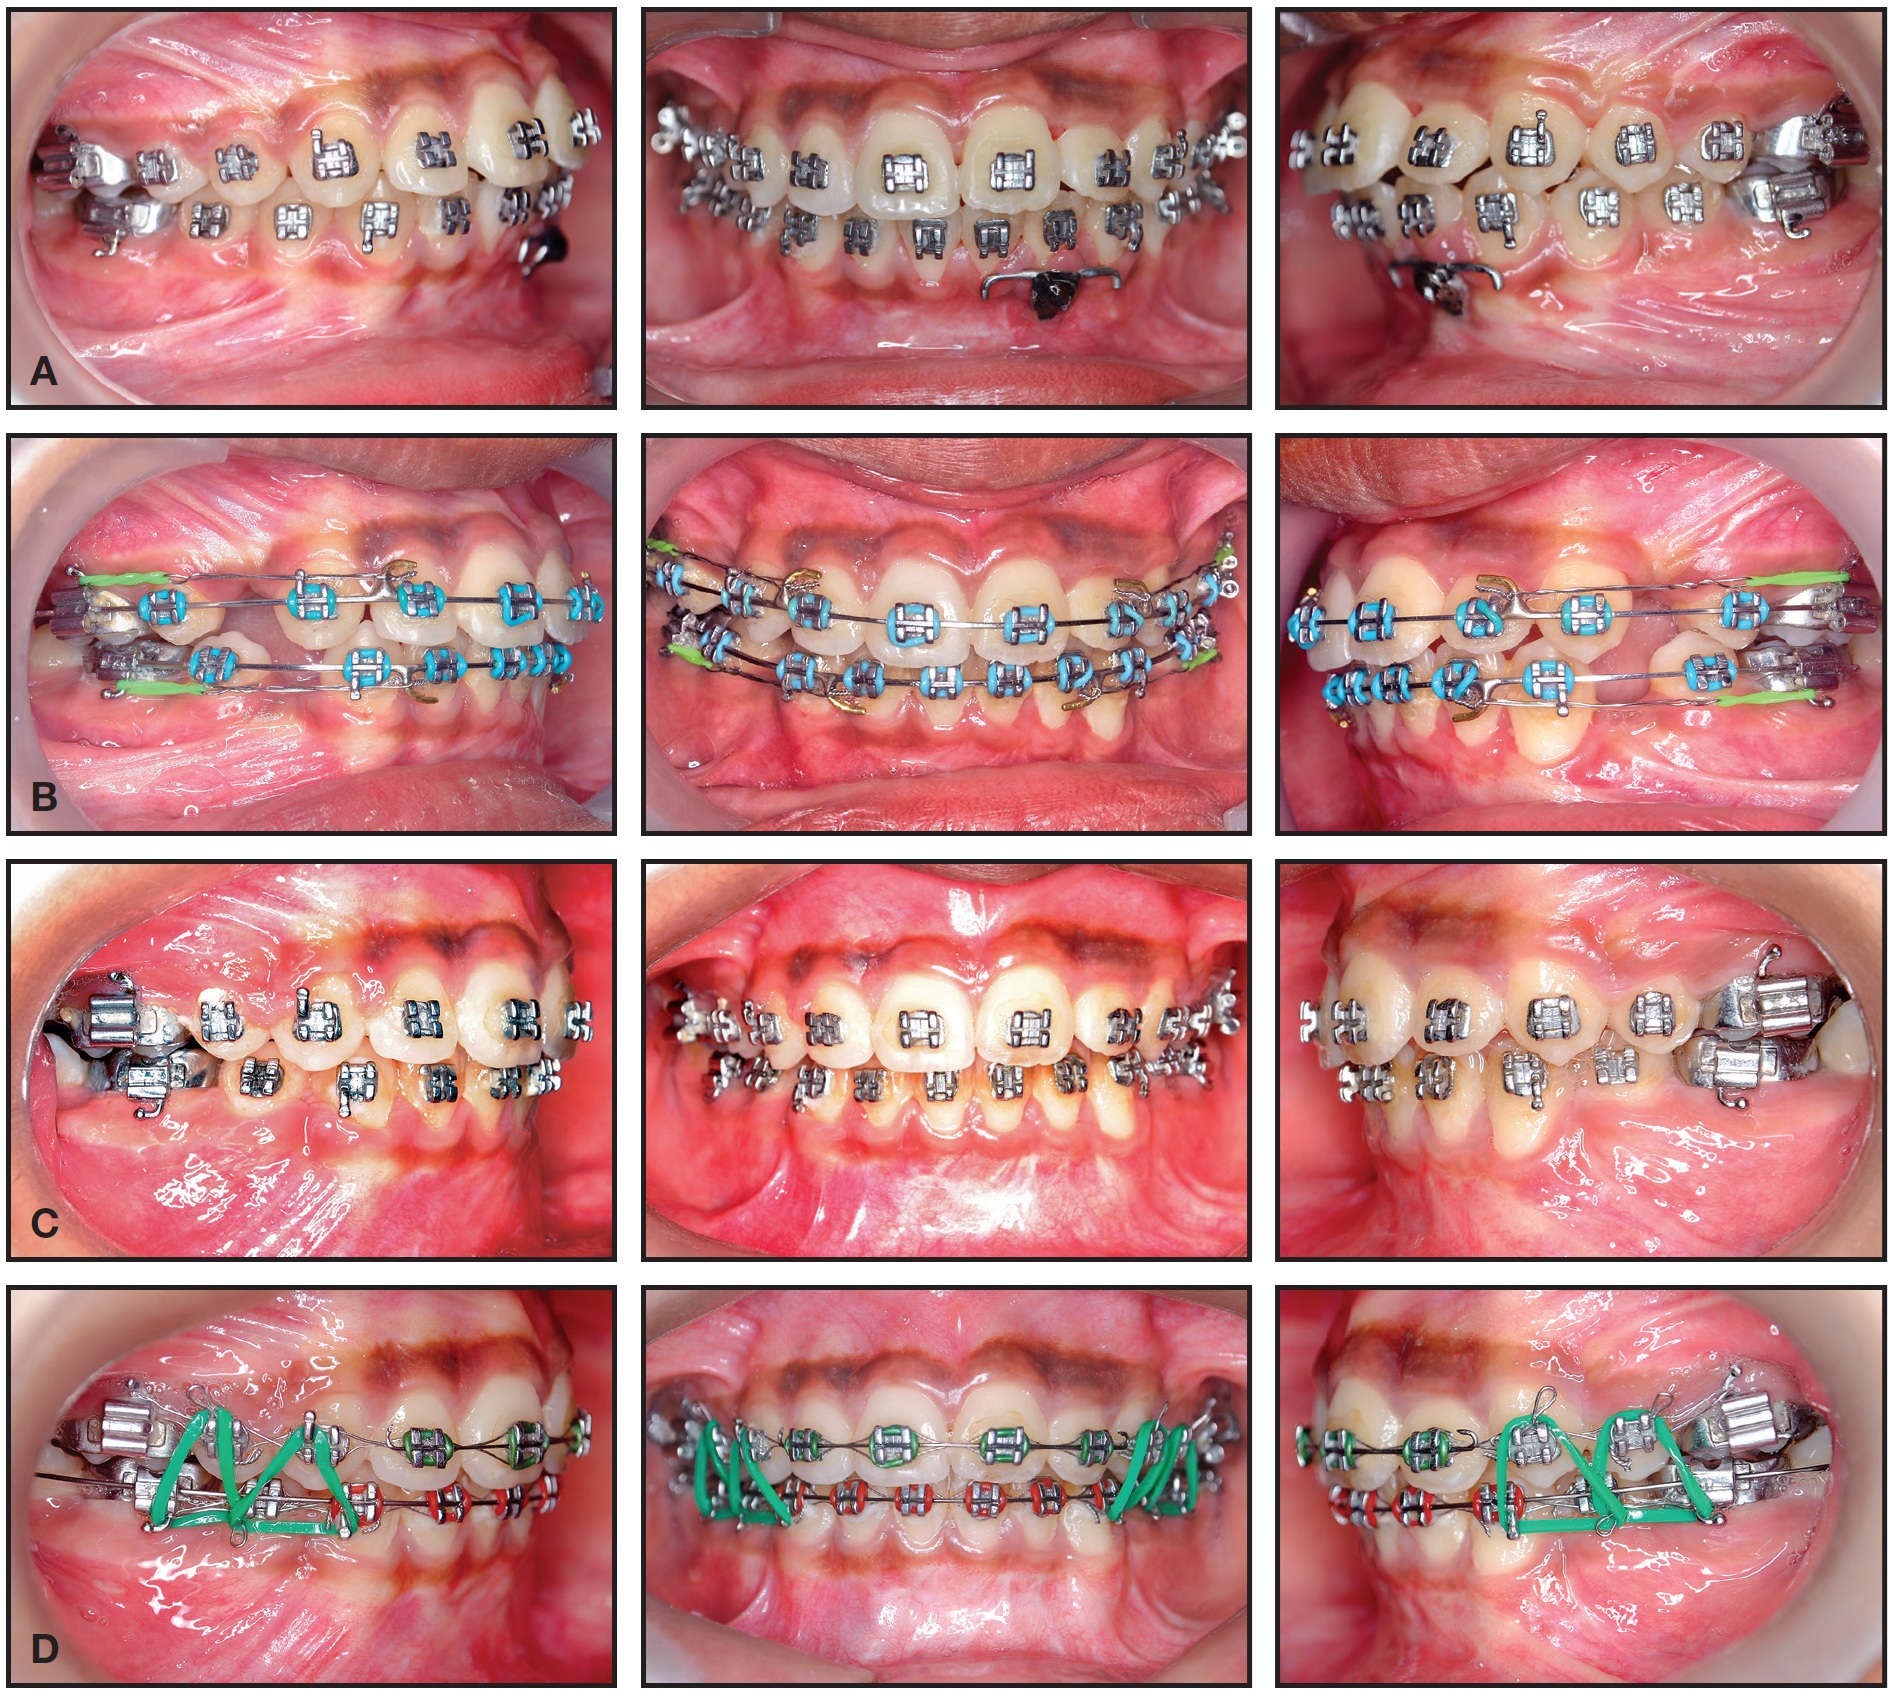

After three more months of upper extrusion and lower intrusion, the remaining teeth were bonded to continue leveling and alignment. Twenty-four weeks later, records were taken and the patient was reevaluated to determine the remaining course of treatment (Fig. 3A). Based on cephalometric and clinical evaluation, all four first premolars were extracted (Fig. 3B). This was followed by retraction of the upper and lower anterior teeth (Fig. 3C) and the use of intermaxillary elastics for final settling (Fig. 3D). Overall active treatment time was 30 months.

Fig. 3 A. Reevaluation after 12 months of traction. B. Three months later, next phase of treatment started after extraction of four first premolars. C. After six months of space closure. D. Intermaxillary elastics used in finishing stage.